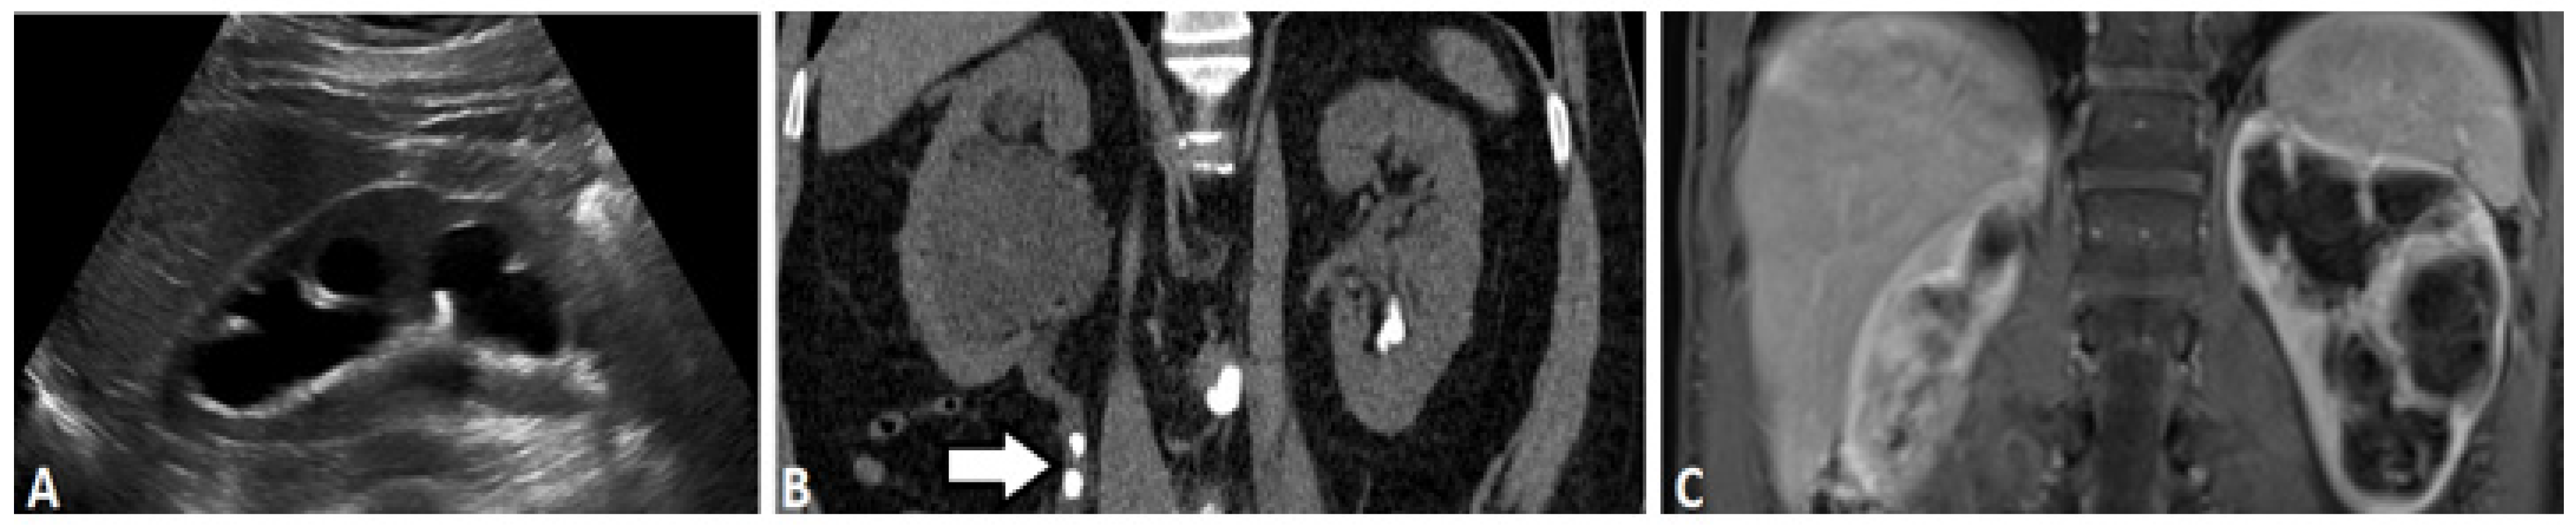

2.1. Ultrasound-Based Urography

2.3. Computed Tomography

2.5. Magnetic Resonance (MR) Based Urography